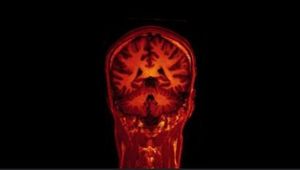

Blick ins Gehirn: KI wertet Scans aus (Foto: Flickr.com/Jon Olav Eikenes) |

Montreal (pte003/31.08.2017/06:10) Wenn Künstliche Intelligenz (KI) die Analyse von Gehirnscans übernimmt, lassen sich frühe Anzeichen von Demenz erkennen und späterer Alzheimer bis zu zwei Jahre im Voraus vorhersagen, so Forscher der McGill University http://mcgill.ca . Sie haben einen Algorithmus entwickelt und trainiert. Beim Praxistest erzielte das System eine Erfolgsquote von 84 Prozent. Eine erste Testversion des Prognose-Tools http://bit.ly/2iHIOSD ist bereits verfügbar.